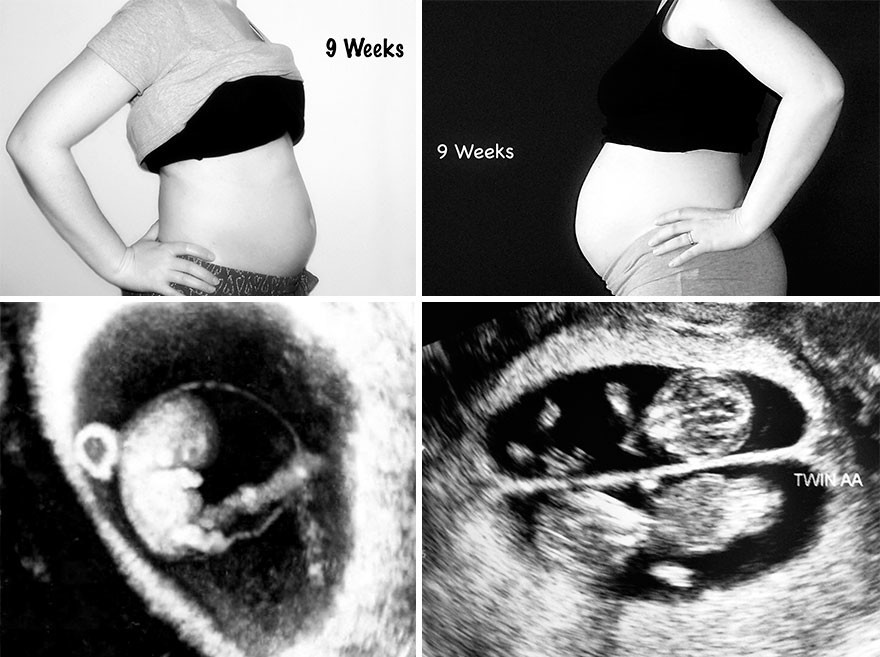

Nueve semanas de embarazo

Gemelos1